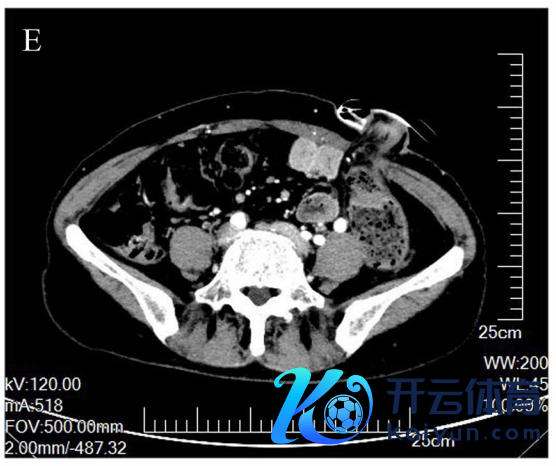

术后胃部CT:窦区胃壁增厚伴周围淋凑趣儿(图1D,E)。

图1D,E. 术后胃CT露馅胃窦胃壁增厚,最厚处直径约22 mm,累及管腔环周,长约150 mm,周围淋凑趣儿教导术后梗阻症状彰着缓解。